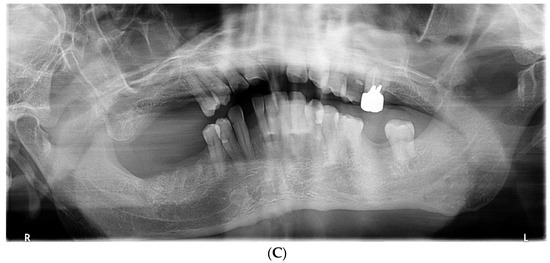

2. Case Presentation

2.1. Day 1: First Examination